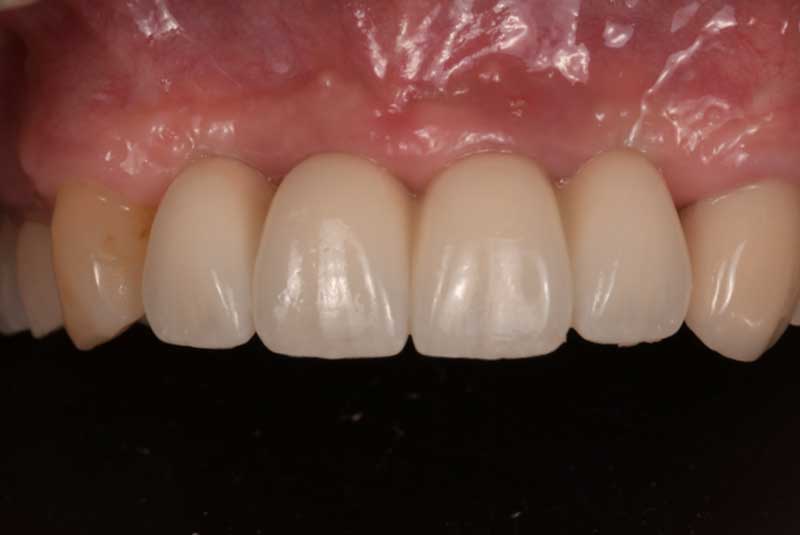

Implant crown #7&19, Crowns (#3,4,5,6,8,9,10,11,12, 13,20,21,22,23,24,25,26,27,28,29) Before & After